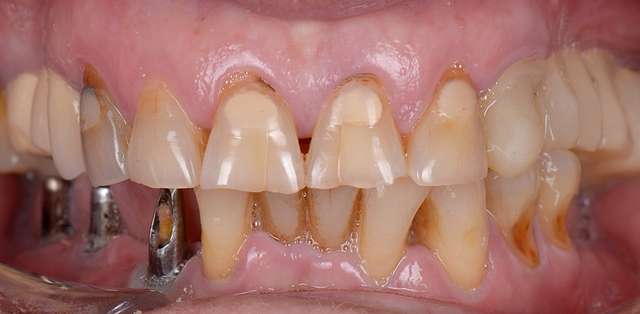

As time goes by, teeth start to wear physiologically, and become shorter. Their proportions start to change and this is perceived as an aging effect. Central dominance is lost, which is one of the main characteristics of a young smile. Gums start to recede and black triangles form in their absence.

And off course the various treatments leave their mark as they reach their lifetime. All of these can be rehabilitated via redesign using ceramic veneers and crowns. Rejuvenation happens as the youthful features are re-embedded in design. Smile rejuvenation is a major component of facial rejuvenation.